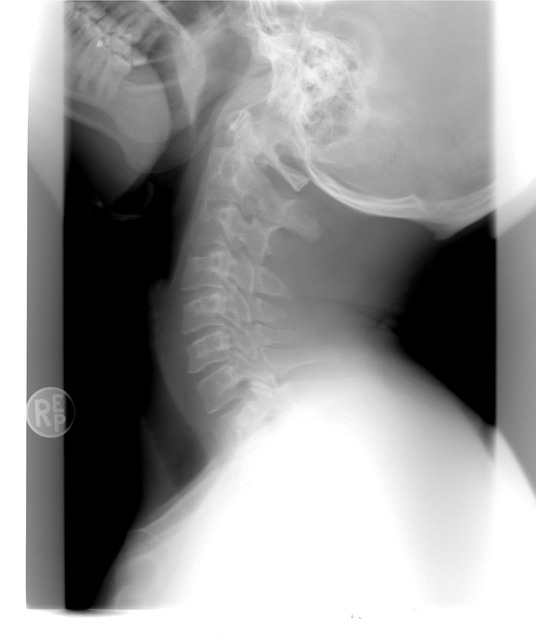

경추 디스크로 인한 통증을 치료하려면 먼저 전문적인 진단이 필요합니다. X-레이나 MRI 촬영을 통해 디스크 상태를 정확히 파악한 후, 적절한 치료법을 선택해야 합니다. 초기 단계에서는 주로 비수술적 치료를 진행합니다. 물리치료와 약물치료를 통해 통증을 완화하고, 디스크 주변 근육을 강화하는 운동을 병행합니다. 필요시 경추 견인 치료를 통해 압박된 신경을 풀어주는 방법도 고려됩니다.

정확한 진단은 의료 전문가의 도움을 받아야 합니다. 병원을 방문하여 X-레이, MRI, 혹은 신경학적 검사를 통해 원인을 확인하고 적절한 치료 계획을 세우는 것이 중요합니다. 치료 계획은 긍정적인 결과로 이어지는 경우가 많으니 적극적으로 계획하시기 바랍니다.